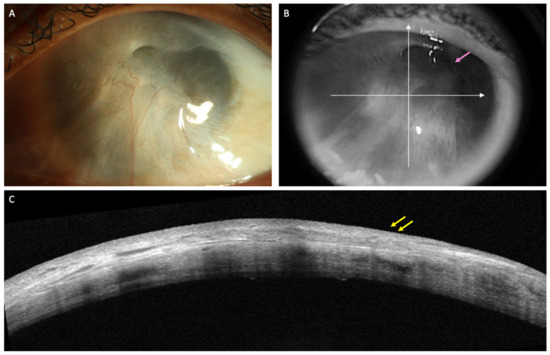

2. Conjunctival Diseases